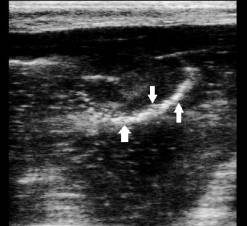

Ультразвуковое исследование матки коров после

оперативного отделения последа выявило наличие остатков плацентарной ткани,

которая визуализируется в виде яркой гиперэхогенной линии на поверхности

карункулов. Стенки матки разрыхленные, эхоструктура неоднородна. В полости

матки содержится большое количество анэхогенной жидкости с хлопьевидными гипер-

и гипоэхогенными включениями, что подтверждает наличие воспалительного процесса

(рис. 1).

Рис. 1. Неотделившаяся плацентарная ткань

на карункуле

(после оперативного отделения последа).